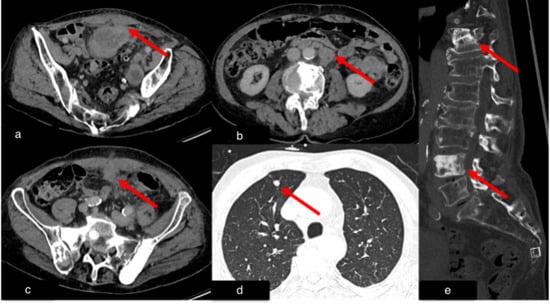

In 45 cases (47.9%), recommendations for follow-up or further evaluation of incidental findings were not pursued by the clinicians (IGN). Follow-up imaging (FI) was performed in 23 cases (24.5%), 4 cases (4.3%) underwent biopsy, 3 cases (3.2%) underwent surgical intervention, and 1 case (1.1%) underwent laboratory testing for Epstein–Barr virus (EBV) (LAB). Fourteen cases (14.9%) were categorized as “other” (OTH), including instances where patients declined further medical evaluation or passed away before additional diagnostic measures could be undertaken. Figure 7 and Figure 8 show examples of potential suboptimal clinical management despite recommendations in the radiological reports.

Figure 7.

Case 4, 66-year-old male with history of marginal zone lymphoma. A chest CT scan was performed after recovering from COVID-19 to assess post-primary changes in the lung. No pathological lung findings were observed. However, an incidental finding of a short dissection in the superior mesenteric artery was noted (red arrow). Additionally, the spleen (blue asterisk) and retroperitoneal lymph nodes (small yellow asterisk) are enlarged, consistent with the underlying disease.

Figure 8.

Case 5, 67-year-old male. A chest CT scan was performed to evaluate for pulmonary embolism after recovering from COVID-19. (a) Axial view, (b) sagittal view. As incidental finding, an abdominal aortic aneurysm was discovered (red arrows).